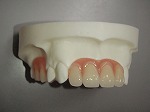

当院の総入れ歯では、リンガライズド・オクルージョンという特別な噛み合わせで製作しております。この噛み合わせの特徴は、小さな力で食品を破砕することが可能となり、顎堤が吸収して食事中、入れ歯の安定が悪い方にお勧めです。

総入れ歯1

総入れ歯2

総入れ歯3